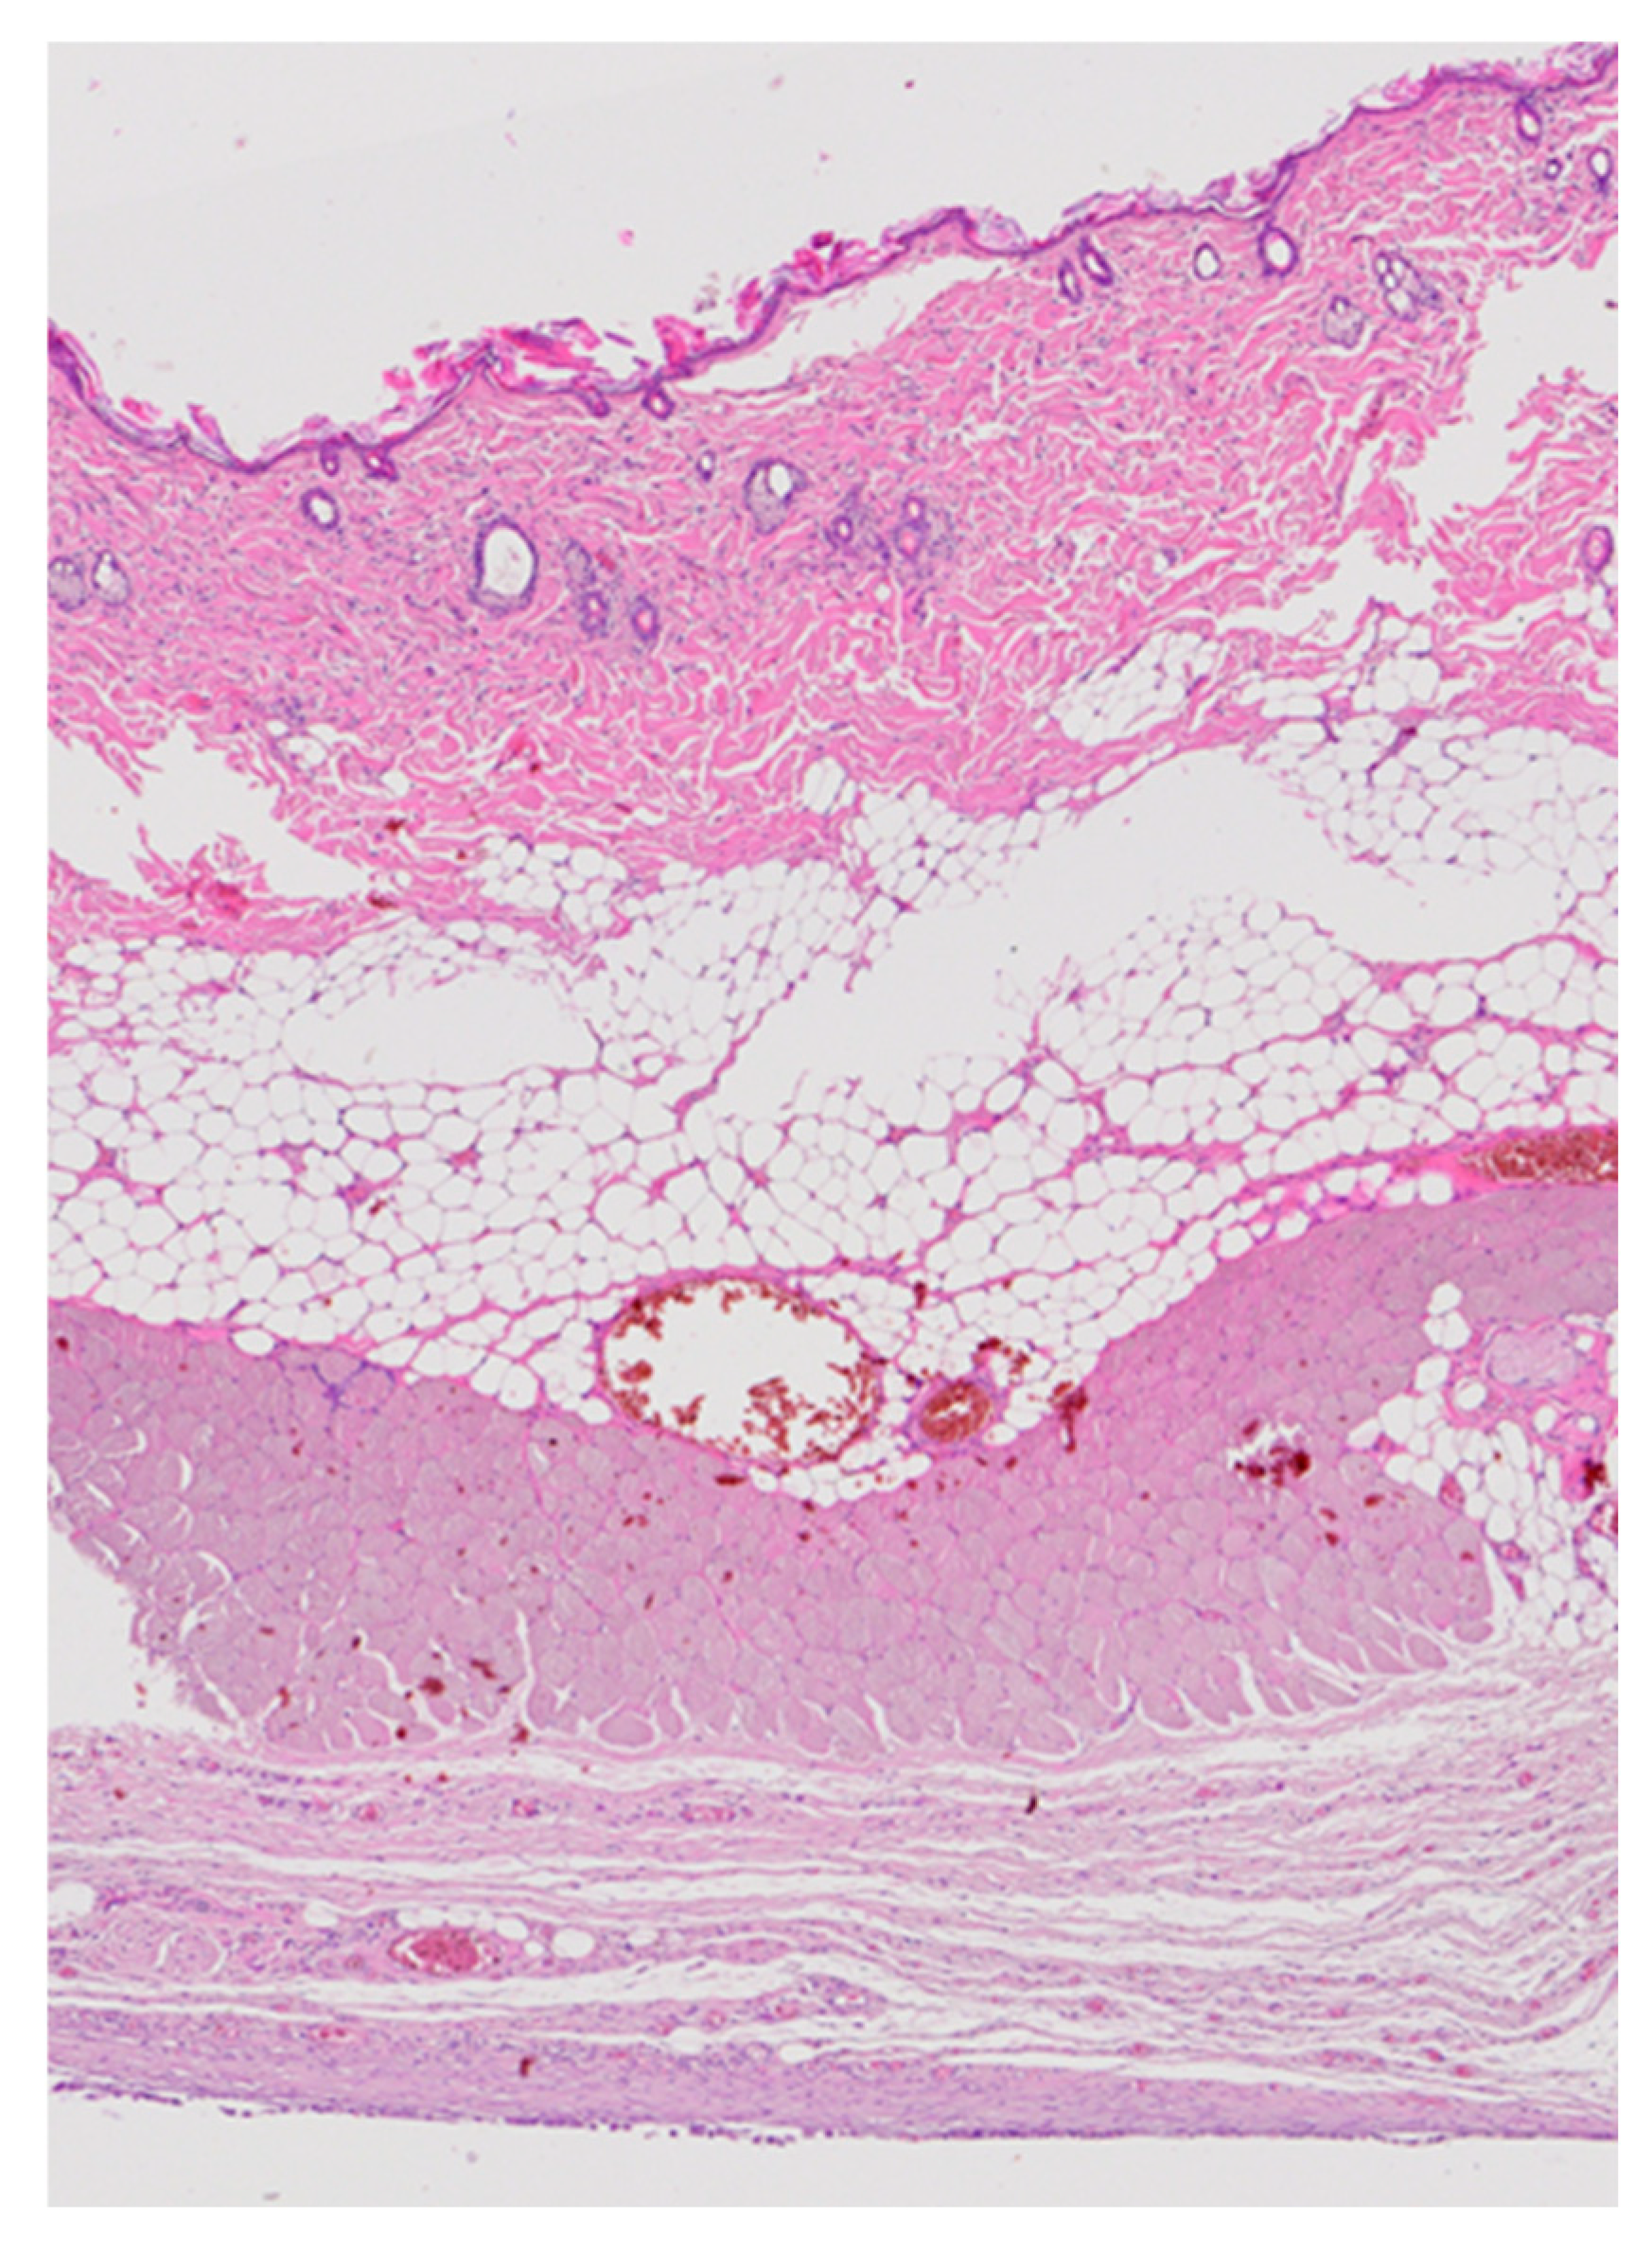

Low-magnification overview images showed normal architecture of the skin, subcutaneous tissue, and underlying muscle at all implantation sites (Figure 9). Both groups displayed normal epidermal and dermal structures, intact adipose tissue, and well-preserved skeletal muscle fibers. No necrosis, abscess formation, or exuberant inflammatory infiltrate was observed. A thin fibrous capsule surrounded the implant in all specimens, consistent with a minimal foreign-body reaction typical for subcutaneous bio-materials in rodents.

Figure 9. Low-magnification overview of the dorsal implantation site showing skin, subcutaneous tissue, adipose tissue, muscle, and developing fibrous capsule (H&E, 20×).